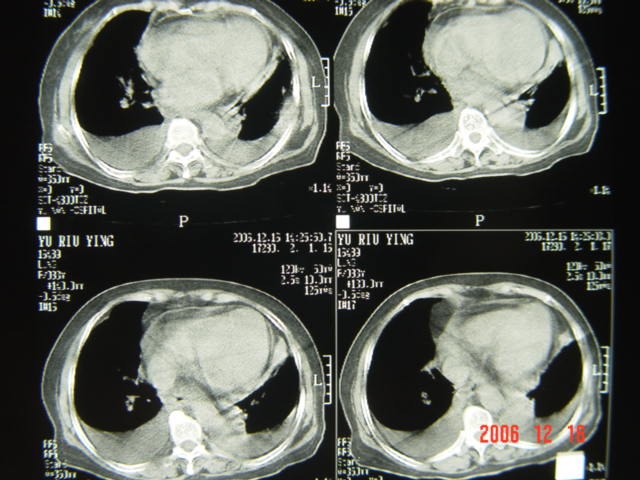

标题: CT5663:女、83岁,轻微咳嗽、左下胸痛。 [打印本页]

标题: CT5663:女、83岁,轻微咳嗽、左下胸痛。

左第八肋腋侧呈膨胀性骨质破坏,内侧见软组织密度肿块。左肺舌段呈楔形实变,基底近胸壁,尖端向肺门。双侧胸壁后缘见新月形水样密度区。

考虑:1、左第8肋骨转移瘤;

2、左肺舌叶肺栓塞可能性大;

3、双侧中量胸腔积液。